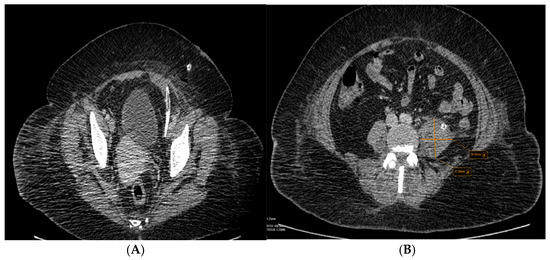

After the preoperative preparation, surgical intervention is performed, and the Dos Santos incision is practiced. After dissection of the anatomical planes, a voluminous abscess is drained from the level of the left psoas muscle, taking cultures from this level simultaneously. It continues with the debridement and washing of the operative area, placing drain tubes at this level, one with the tip located in the left paravesical pelvis (Figure 5A) and one with an ascending trajectory along the left iliopsoas muscle (Figure 5B) and the tip on its ventral side, next to the L3 vertebral body, as can be seen in the second abdominal and pelvis CT scan with contrast substance performed after surgical drainage. The drain tubes were removed after nine days. The primary intention was chosen from the perspective of wound healing. The abscess was treated surgically with incision and drainage, and the wound was relatively clean. The wound’s edges were brought together and healed with minimal scarring.

Figure 5.

(A,B) The second abdominal and pelvis CT scan with contrast substance was performed after surgical drainage, which can be seen in the drain tubes.